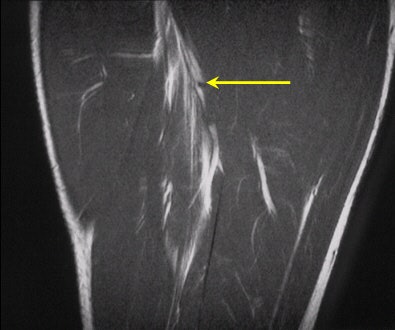

| Hyperintensity of the proximal portion of the long head of biceps femoris muscle is compatible with a strain (arrow). |

MR imaging is noted to be more sensitive in the detection of soft-tissue injury compared to ultrasound, particularly in the setting of edema without visible macroscopic disruption. MRI scans demonstrated edema and hemorrhage as bright signal on proton-density sequences, which acts as a direct contrast with the gray isointense signal of muscle. This accounts for the high sensitivity of this modality, as well as the benefits of multiplanar capability (also a benefit of sonography).